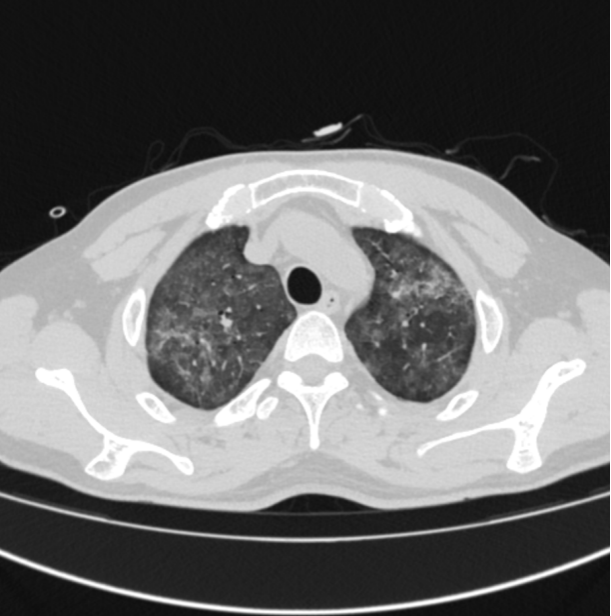

影像学检查 图1~4胸部CT均可见双肺弥漫性磨玻璃灶。

图1~4 CT平扫均可见双肺弥漫性磨玻璃样改变(GGO),对称分布,图3可见病变由肺门向外周带扩散。

PCP是一种机会致病菌,常见于免疫功能低下患者,如艾滋病、长期使用免疫抑制类药物患者。本例患者在接诊初期未询问冶游史,HIV抗体阳性后追问补充病史。临床表现主要以干咳为主,伴有进行性呼吸困难,发热、腹胀、乏力等。PJP影像学表现为GGO,多内带分布,由肺门朝外,从中央向外周扩散,呈大片状或蝶翼征,双肺对称或不对称,可伴有腺泡结节、空气支气管征、铺路石征、实变及纤维条索状。CMP表现为急性间质性肺炎,伴有弥漫性肺泡水肿和纤维蛋白渗出物,典型影像学为GGO及微小结节。免疫功能低下患者,出现呼吸困难、低氧血症和影像学磨玻璃样改变时,应考虑到肺孢子菌及病毒性肺炎(如巨细胞病毒性肺炎等)的可能。